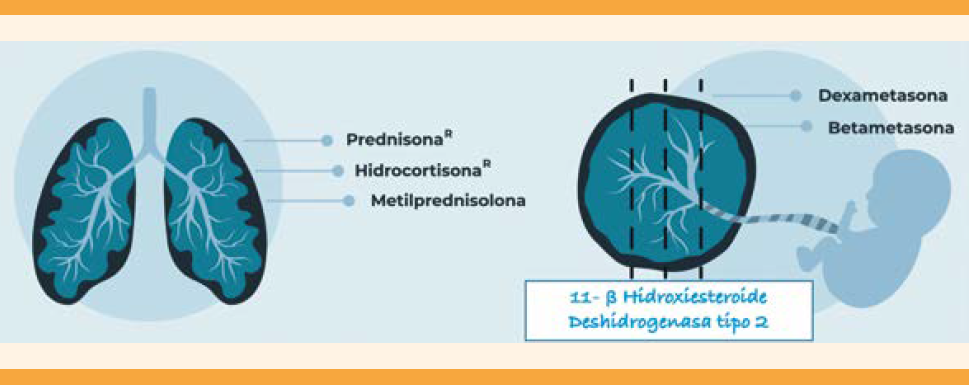

Esteroides, COVID-19 y embarazo

La indicación de corticosteroides a pacientes con COVID-19 tiene dos opciones precisas: favorecer la inducción de la maduración pulmonar fetal ante un alto riesgo de nacimiento pretérmino inminente (próximos 7 días) y como tratamiento para casos graves. Es importante ser precisos ante la decisión de recurrir a esta intervención. La administración de corticosteroides durante un lapso prolongado está contraindicada porque reduce los movimientos corporales y respiratorios del feto. Además, puede propiciar la restricción del crecimiento fetal, bajo peso al nacimiento, hipoglucemia fetal, aumento de la incidencia de sepsis neonatal y mayor riesgo de trastornos de conducta y mentales en la edad pediátrica.82,83,84 Los glucocorticoides activan múltiples mecanismos que favorecen la diferenciación tisular, con influencia en la programación fetal con repercusiones fisiológicas hepáticas, pulmonares, suprarrenales, intestinales, renales, cerebrales y en el tejido adiposo que favorecen la aparición de enfermedades crónicas del adulto.85,86 Figura 6

En caso de riesgo de parto prematuro inminente (menos de 34 semanas, más de 3 cm de dilatación cervical o borramiento) se indica la administración de un ciclo corto de dexametasona o betametasona para acelerar la maduración pulmonar fetal. En caso de COVID-19 grave los desenlaces del síndrome respiratorio agudo mejoran con la terapia prolongada con esteroides en dosis bajas.87,88 El estudio RECOVERY demostró que la administración de dexametasona se asocia con menor riesgo de mortalidad entre las personas que requieren oxígeno suplementario (en el caso de las pacientes embrazadas iniciar ante SpO2 < 94%) y cuando requieran ventilación mecánica por COVID-19. Con un esquema de 6 mg por vía oral o intravenosa cada 24 horas, durante un máximo de 10 días.81,89,90 Cuadro 11

Cuadro 11 Sugerencias para la indicación de corticosteroides en COVID-19 y embarazo

| Esteroides COVID y embarazo | |

|---|---|

| SFMF (Medicine, 2021) | Esquema de madurez pulmonar fetal: dexametasona 6 mg IM c/ 12 h durante 48 h (4 dosis) seguido de 6 mg VO / IV cada 24 h hasta completar un total de 10 días. Sin esquema de madurez pulmonar fetal: 6 mg VO / IV cada 24 h por 10 días. |

| ACOG (87) | Esquema de madurez pulmonar fetal: dexametasona 6 mg IM c/ 12 h durante 48 h (4 dosis) seguido de Metilprednisolona 32 mg VO / IV cada 24 h hasta completar un total de 10 días. Sin esquema de madurez pulmonar fetal: metilprednisolona 32 mg VO / IV cada 24 h hasta completar un total de 10 días. |

| RCOG /RECOVERY trial19 | Esquema de madurez pulmonar fetal: dexametasona 6 mg IM c/ 12 h durante 48 h (4 dosis) seguido de prednisolona 40 mg VO / IV cada 24 h o hidrocortisona 80 mg VO / IV cada 12 h hasta completar un total de 10 días. Sin esquema de madurez pulmonar fetal: prednisolona 40 mg VO / IV cada 24 h o hidrocortisona 80 mg VO / IV cada 12 h hasta completar un total de 10 días. |

*Esquema de madurez pulmonar en ≤34 semanas de gestación.